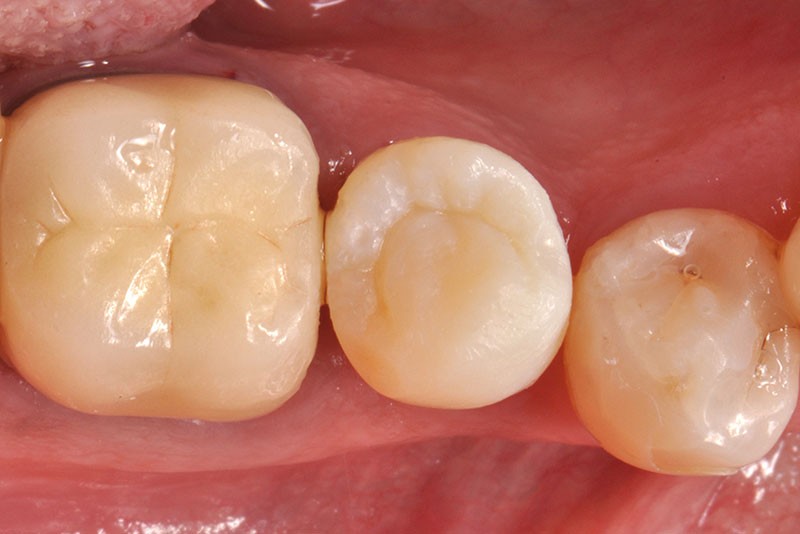

34, 35. Vues vestibulaire et occlusale de la prothèse d’usage collée sur 45 (Laboratoire du Sud-Ouest).